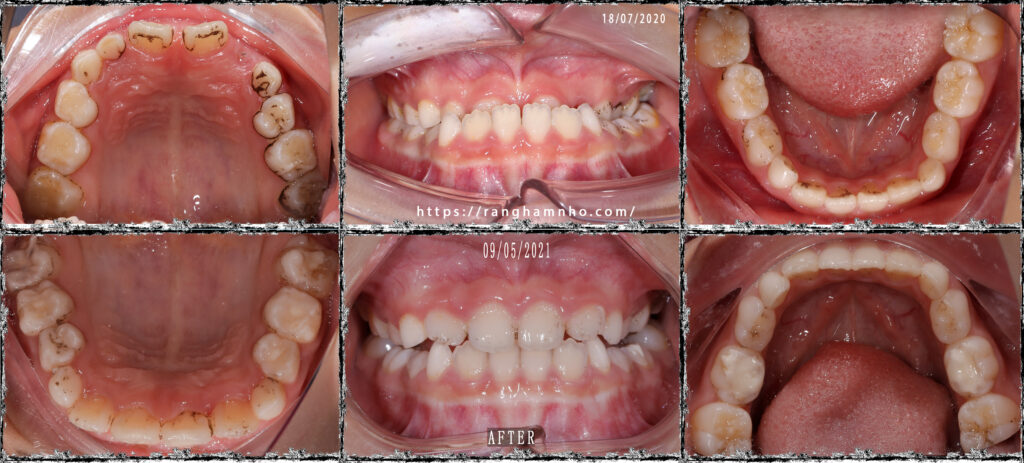

Ảnh cung hàm trước và sau điều trị nong hàm

Ảnh khớp cắn: khớp cắn răng sữa sẽ tự đóng sau 1-2 tháng